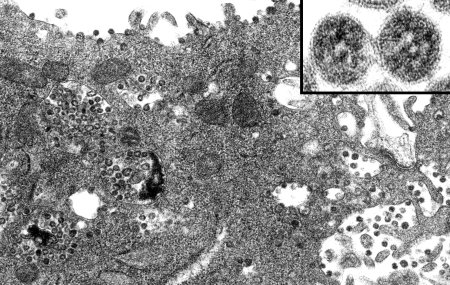

Коронавирус микроскопия